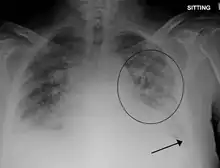

Low oxygen saturation in blood and disturbed arterial blood gas readings support the proposed diagnosis by suggesting a pulmonary shunt. A chest X-ray will show fluid in the alveolar walls, Kerley B lines, increased vascular shadowing in a classical batwing peri-hilum pattern, upper lobe diversion (biased blood flow to the superior parts instead of inferior parts of the lung), and possibly pleural effusions. In contrast, patchy alveolar infiltrates are more typically associated with noncardiogenic edema[3]